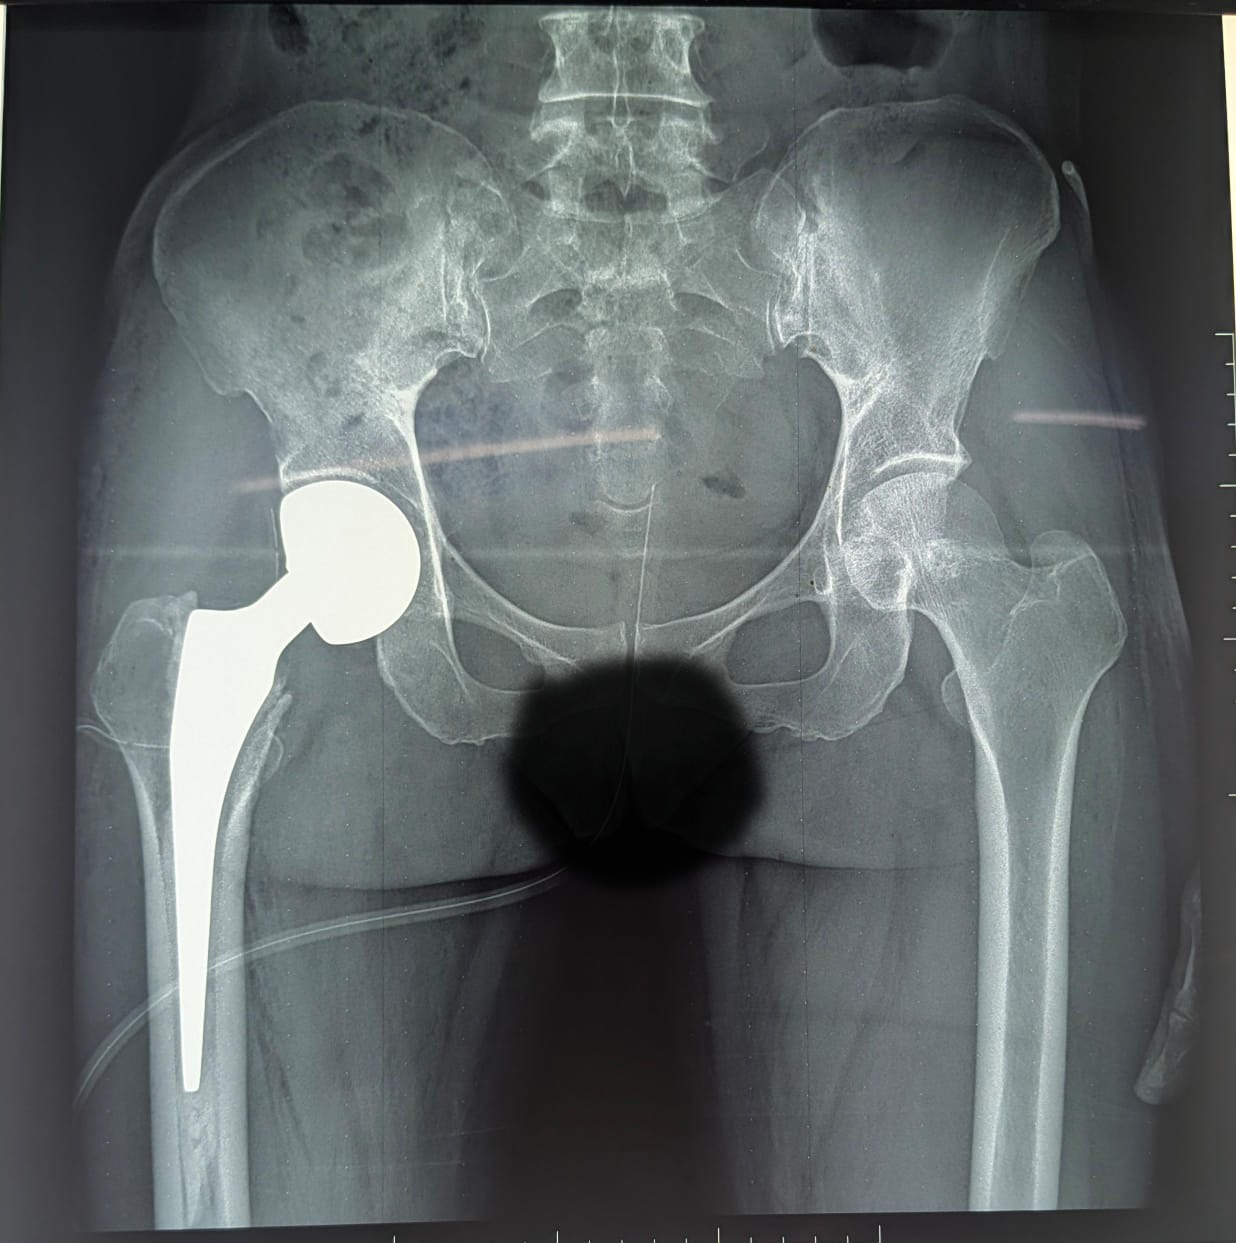

Au CHR Kaya, chaque patient bénéficie d’un suivi attentif et de soins de haute qualité, comme en témoigne le cas récent d’une patiente de 65 ans admise le 05 mars 2026 pour une fracture fermée de la hanche droite, type IV de Garden, survenue il y a un mois. Initialement alitée à domicile, elle a pu bénéficier d’une prothèse intermédiaire totalisable de la hanche droite.

Grâce au renforcement continu de son plateau technique et à l’expertise de l’équipe chirurgicale dirigée par le Dr OUEDRAOGO Hermann chirurgien orthopédiste traumatologue, des anesthésistes conduite par Dr LOMPO Fabrice des soins spécialisés sont de plus en plus disponibles. Nous notons l’engagement sans failles des collaborateurs infirmiers, médecins généralistes de l’unité du post opéré, du kinésithérapeute ainsi que des Garçons et Filles de salle dévoués qui ont rendu les suites opératoires simples. La patiente a retrouvé sa mobilité et repris la marche dès le lendemain (J1) de son intervention, illustrant parfaitement l’efficacité et la rapidité des soins prodigués.